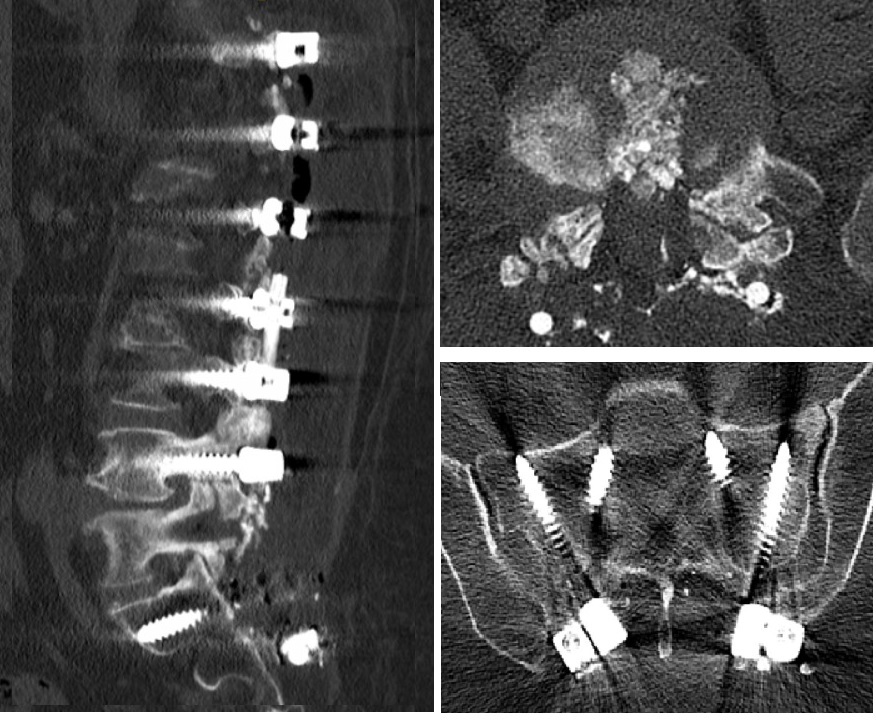

2022 Yılı BT İncelemesi - Vida Gevşemesi

Resim 3: BT incelemesinde T10-T11 ve L4-L5 diskleri içinde ve ayrıca kanal içinde L4 korpusu arkasında gaz ile uyumlu hipodansite, L4 ve L5 vidalarında iki yanlı gevşeme ve foraminal stenozlar görülüyor. Ayrıca L3-4 ve L4-5 seviyelerinde faset füzyonlarının tam oluşmadığı görülmekte. Diğer vidalarda gevşeme ya da malpozisyon yoktur.

Postop AP Radyolojik Görüntü Postop Lateral Radyolojik Görüntü

Resim 7: Ameliyat sonrası (postop) direkt grafiler. PEEK rod ile dinamik stabilizasyon uygulanmıştır.

Ameliyatta eski ensizyon açılarak titanyum rodlar çıkartıldı. L4-5 seviyesi açılarak kanal içi ve foramen çıkışları dekomprese edildi. Disk içi boşaltılarak otojen kemik greft ile dolduruldu. Gevşemiş L4 ve L5 vidaları çıkartıldı. L4 vidaları kalın vidalarla değiştirildi, L5 seviyesine vida konmadı. S1 ve S2 seviyelerine vida kondu (S1 medial ve kaudal yönelimli, S2 vidaları laterale ve kraniuma yönelimli). L2 vidalarından S2 vidalarına uzanan birer PEEK rod ile sistem stabilize edildi.